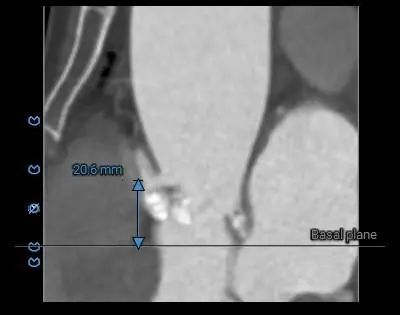

主动脉瓣环水平夹角71度,严重横位心,主动脉弓宽度、角度尚可,弓部存在散在钙化

虚拟瓣环与水平夹角